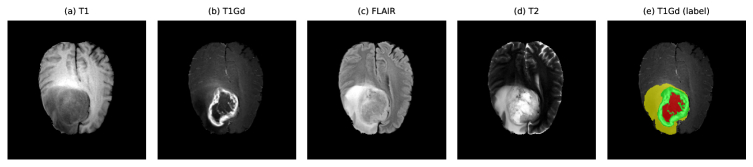

Refer to caption

Figure 1: All four channels of a sample BraTS-GLI patient and the corresponding manual segmentation overlaid on the T1Gd image. From left to right: T1, T1Gd, FLAIR, T2, and T1Gd with label map (red = NCR/NET, yellow = ED, green = ET). Figure created by Anthony Joon Hur using Python.

I use the BraTS 2023 Adult Glioma (GLI) Task 1 dataset, which builds on the BraTS benchmark series and the underlying TCGA-GBM and TCGA-LGG collections [2, 14, 10, 11, 12]. Each case consists of four co-registered MRI modalities (T1, T1Gd/T1c, T2, FLAIR) at 11 mm3 resolution and a segmentation mask with labels {0,1,2,4}\{0,1,2,4\} for background, necrotic or non-enhancing tumor, edema, and enhancing tumor, respectively. Figure 1 illustrates one example BraTS-GLI case and highlights the visual differences between modalities and the corresponding label map.